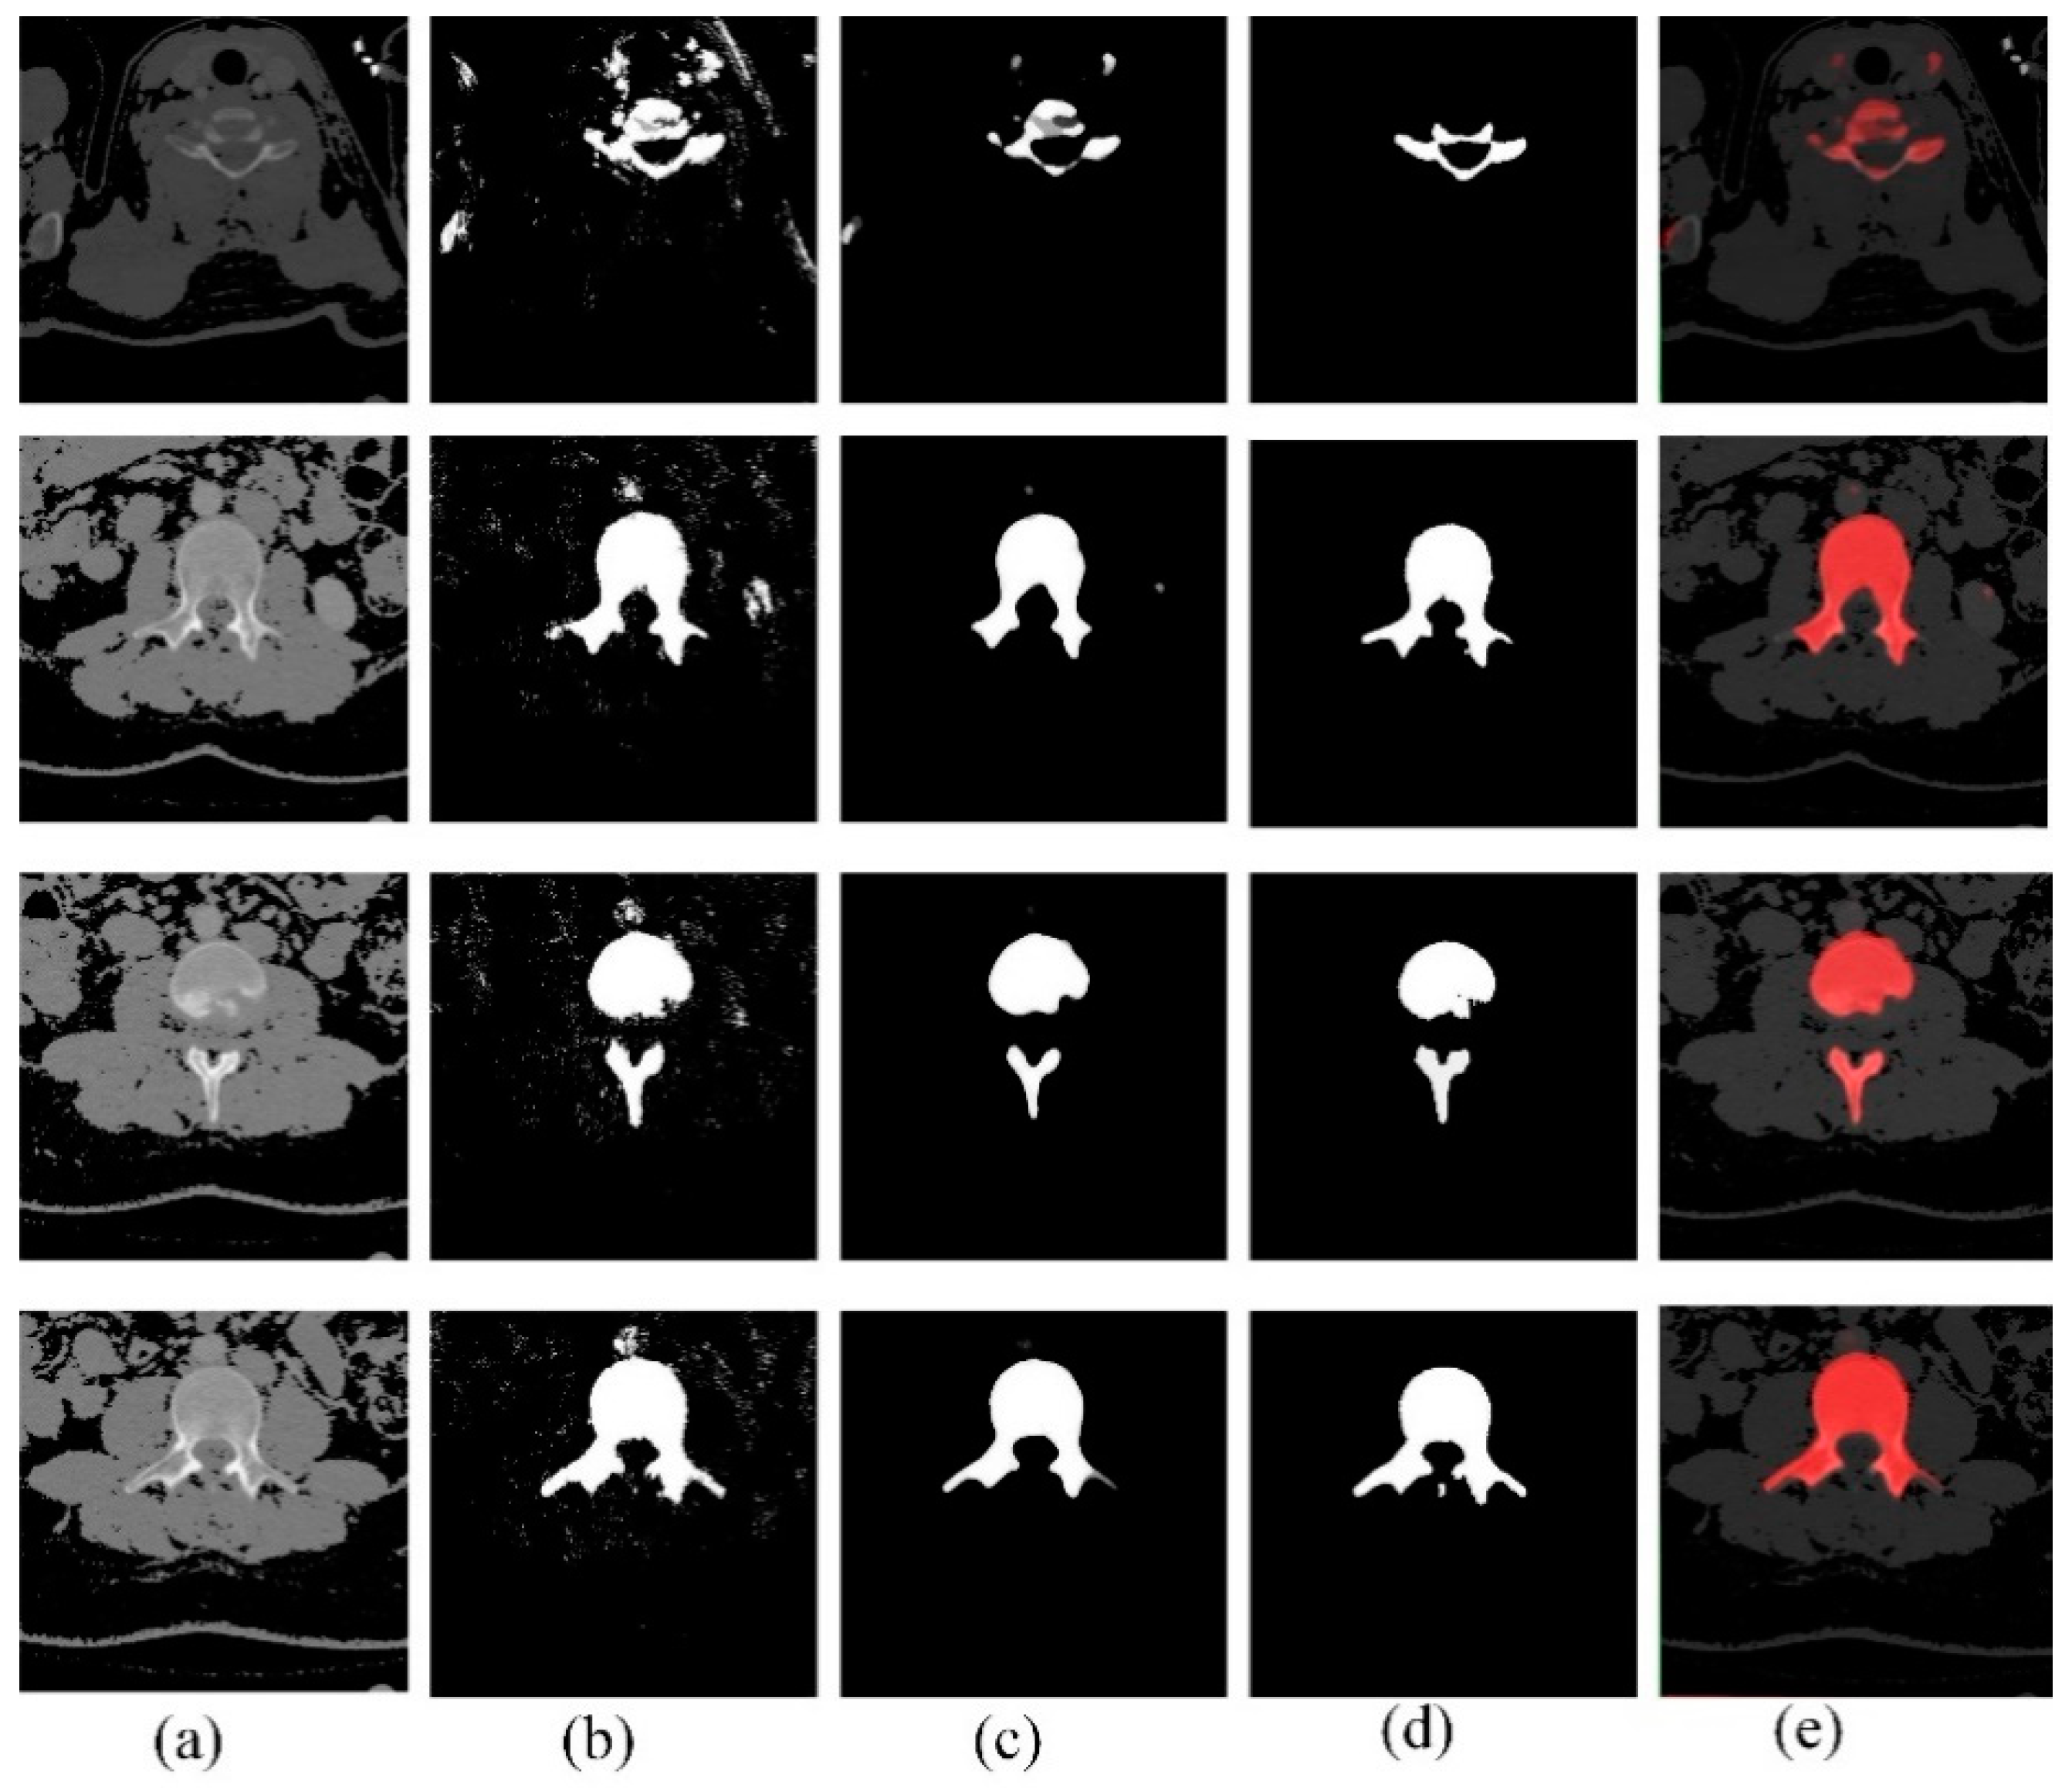

2.4. Segmentation